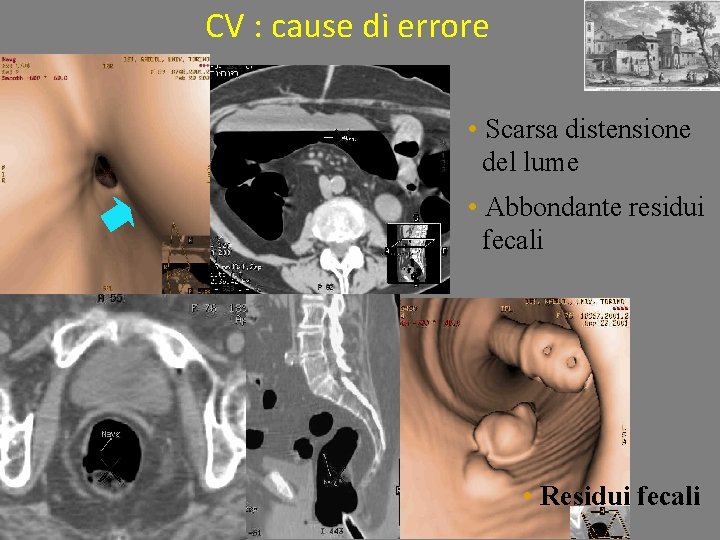

CV : cause di errore • Scarsa distensione del lume • Abbondante residui fecali • Residui fecali